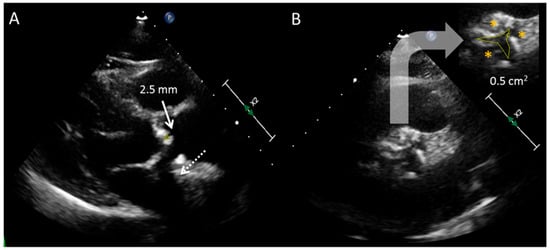

2.2. Transesophageal Echocardiography

- Morelli, S.; De Castro, S.; Cartoni, D.; Perrone, C.; Beni, S.; Bernardo, M.L.; Ferrante, L.; Giordano, M. Planar determination of the aortic valve area with transesophageal echocardiography with multiplanar probe in patients with aortic stenosis and insufficiency. Comparison with transthoracic Doppler echocardiography. G. Ital. Cardiol. 1995, 25, 851–857. [Google Scholar]

- Tribouilloy, C.; Shen, W.F.; Peltier, M.; Mirode, A.; Rey, J.-L.; Lesbre, J.-P. Quantitation of aortic valve area in aortic stenosis with multiplane transesophageal echocardiography: Comparison with monoplane transesophageal approach. Am. Heart J. 1994, 128, 526–532. [Google Scholar] [CrossRef]

- Hoffmann, R.; Flachskampf, F.A.; Hanrath, P. Planimetry of orifice area in aortic stenosis using multiplane transesophageal echocardiography. J. Am. Coll. Cardiol. 1993, 22, 529–534. [Google Scholar] [CrossRef] [PubMed]

- Goland, S.; Trento, A.; Iida, K.; Czer, L.S.C.; De Robertis, M.; Naqvi, T.Z.; Tolstrup, K.; Akima, T.; Luo, H.; Siegel, R.J. Assessment of aortic stenosis by three-dimensional echocardiography: An accurate and novel approach. Heart 2007, 93, 801–807. [Google Scholar] [CrossRef]

- Saura, D.; de la Morena, G.; Flores-Blanco, P.J.; Oliva, M.J.; Caballero, L.; González-Carrillo, J.; Espinosa, M.D.; López-Ruiz, R.N.M.; García-Navarro, M.D.M.; Valdés, M. Aortic valve stenosis planimetry by means of three-dimensional transesophageal echocardiography in the real clinical setting: Feasibility, reliability and systematic deviations. Echocardiography 2015, 32, 508–515. [Google Scholar] [CrossRef]

- Jainandunsing, J.S.; Mahmood, F.; Matyal, R.; Shakil, O.; Hess, P.E.; Lee, J.; Panzica, P.J.; Khabbaz, K.R. Impact of three-dimensional echocardiography on classification of the severity of aortic stenosis. Ann. Thorac. Surg. 2013, 96, 1343–1348. [Google Scholar] [CrossRef]

- Beneduce, A.; Capogrosso, C.; Moroni, F.; Ancona, F.; Falasconi, G.; Pannone, L.; Stella, S.; Ingallina, G.; Melillo, F.; Ancona, M.B.; et al. Aortic valve area calculation using 3D transesophageal echocardiography: Implications for aortic stenosis severity grading. Echocardiography 2020, 37, 2071–2081. [Google Scholar] [CrossRef]